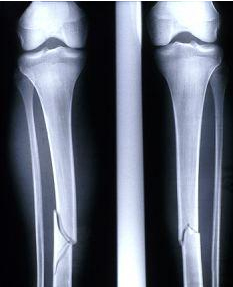

腿部骨折通常是由于交通事故或體育運動導致。